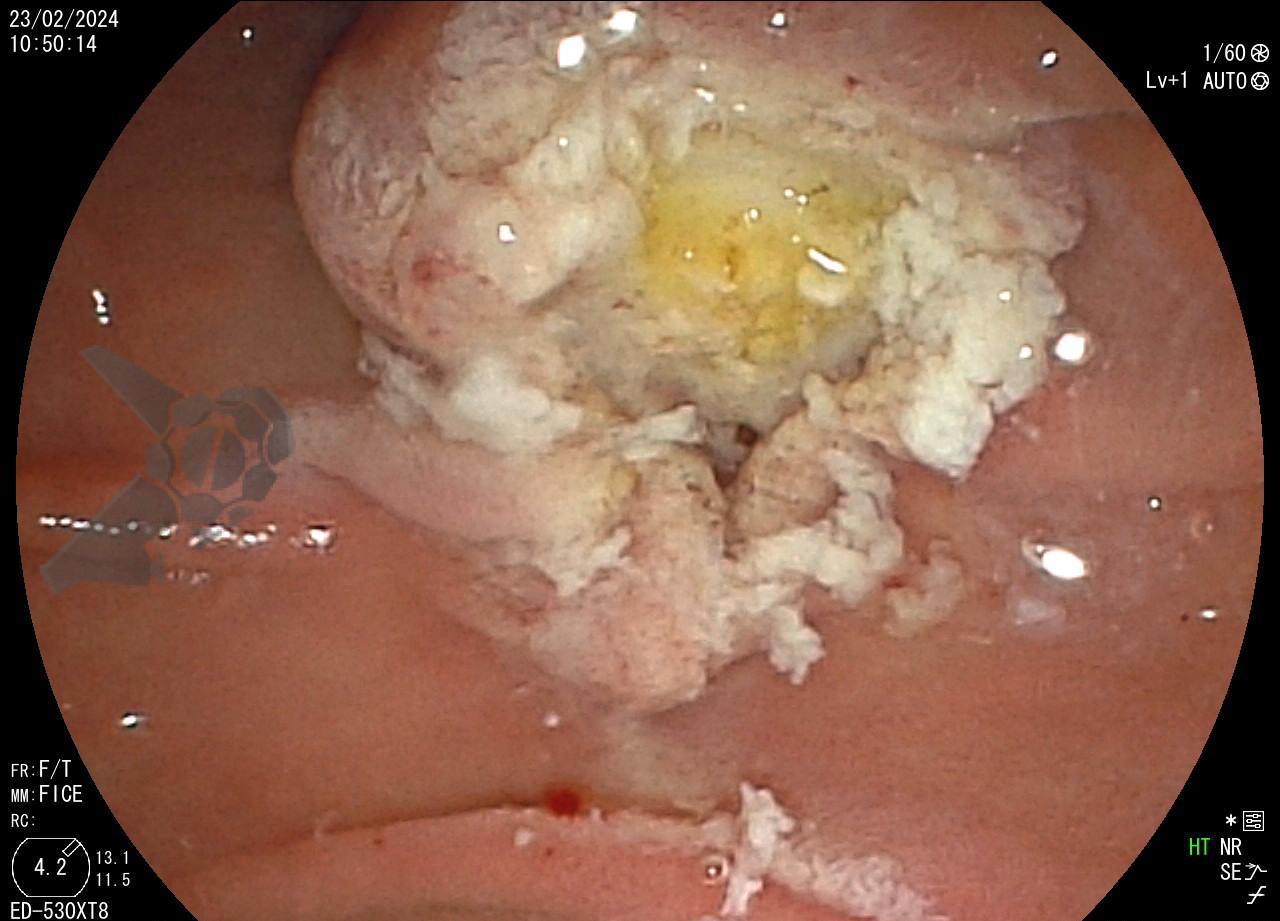

Tendo em vista quadro clínico associado a dilatação de vias biliares, foi indicada colangiopancreatografia endoscópica retrógrada (CPRE) para tratamento de possível estenose da anastomose biliar. Ao se posicionar o duodenoscópio na segunda porção duodenal, identificada lesão polipóide suspeita para adenoma de papila duodenal maior, sendo realizadas biópsias.

Diante da confirmação histológica de adenoma tubular com displasia de baixo grau, optado pelo estadiamento local através de ultrassom endoscópico (EUS), evidenciando lesão restrita a mucosa (sem sinais de acometimento de camada muscular) medindo 12×9 mm, com dilatação de colédoco até 9 mm e ausência de extensão intraductal.

Dessa forma, indicada papilectomia endoscópica e realizada ressecção em monobloco, em modo endocut Q, sem injeção de submucosa. Não foi realizada esfincterotomia ou passagem de prótese biliar ou pancreática. Observou-se pequeno sangramento imediato no leito de ressecção, controlado com injeção de adrenalina. Não há lesão residual no leito. Paciente evoluiu bem, assintomática e sem intercorrências após o procedimento.

Tendo em vista a visão parcial da papila duodenal maior obtida através do endoscópio de visão frontal, sugere-se que a adequada avaliação seja realizada com o duodenoscópio ou endoscópio convencional associado ao uso de cap. Embora não exista uma classificação validada para avaliação das lesões de papila, deve-se avaliar o tamanho, se há extensão da lesão para além da papila, como as lesões de crescimento lateral (LSTp). Além disso, alguns aspectos identificados correlacionam-se com maior risco de invasão da muscular como endurecimento, ulceração, friabilidade, sangramento, depressão e “nonlifting sign”4,5. O diagnóstico histológico deve ser realizado idealmente pela biopsia endoscópica; em caso de falha diagnóstica, são alternativas a biópsia por EUS ou biópsia endoscópica após esfincterotomia, de preferência com intervalo de 10 dias entre os procedimentos4. Vale ressaltar que a presença de adenoma nas biópsias endoscópicas não exclui a presença de adenocarcinoma, devido as altas taxas de falsos negativos e variável concordância entre as biópsias endoscópicas e as peças de ressecção5.